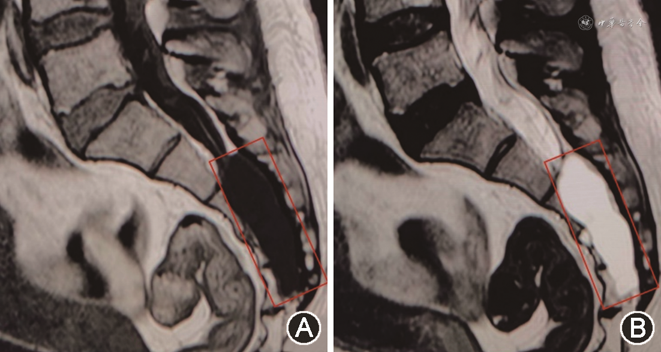

患者女性,55岁,慢性病程。患者自诉于2021年9月初无明显诱因偶发骶尾部疼痛不适感,起初程度轻微,不影响正常生活,后症状迁延,骶尾部疼痛发作频繁且程度加重,严重制约患者日常生活及工作。2021年10月4日入住甘肃省人民医院并于次日完善骶椎MRI检查,结果示骶椎椎管内见一类椭圆形长T1、长T2信号影,长径约2.5 cm(图1)。结合患者病史及影像学资料初步诊断为骶管囊肿。入院体检:骶尾部压痛,其余各项体检结果均未见明显异常。术前完善相关检查,排除手术禁忌证,于2021年10月10日全身麻醉下行后正中入路显微镜下骶管囊肿切除术与脊神经粘连松解术,于麻醉苏醒后返回我科神经重症监护室,予以重症监护,患者嗜睡,轻度恶心,无呕吐,约10 min后患者突发呼之不应,右侧瞳孔散大,直径约5.0 mm,直接及间接对光反射消失,左侧瞳孔直径约2.5 mm,直接及间接光反应灵敏,急予250 ml甘露醇快速静脉点滴并急诊完善头部CT,CT影像学检查结果提示:右侧额顶颞枕部硬膜下血肿,中线由右向左偏移,环池欠清,脑干受压明显(图2)。患者病情危重,遂急在全身麻醉下行右额颞开颅硬膜下血肿清除+骨瓣还纳术,术中未见颅骨骨折、颅内原发性损伤病灶。术后6 h后患者意识状态逐渐恢复,复查头颅CT提示硬膜下血肿清除干净,中线居中,颅内无再出血及梗死表现(图3)。术后采取头高足低位,予以控制颅内压、补液及营养支持等对症治疗后好转离院。定期随访观察并于出院7个月后我院复查头颅MRI提示:右侧额顶颞枕部颅板下片状混杂信号,等T1、长T2信号,脑沟、裂、池未见受压影像,中线结构居中(图4)。患者恢复良好,无明显后遗症。